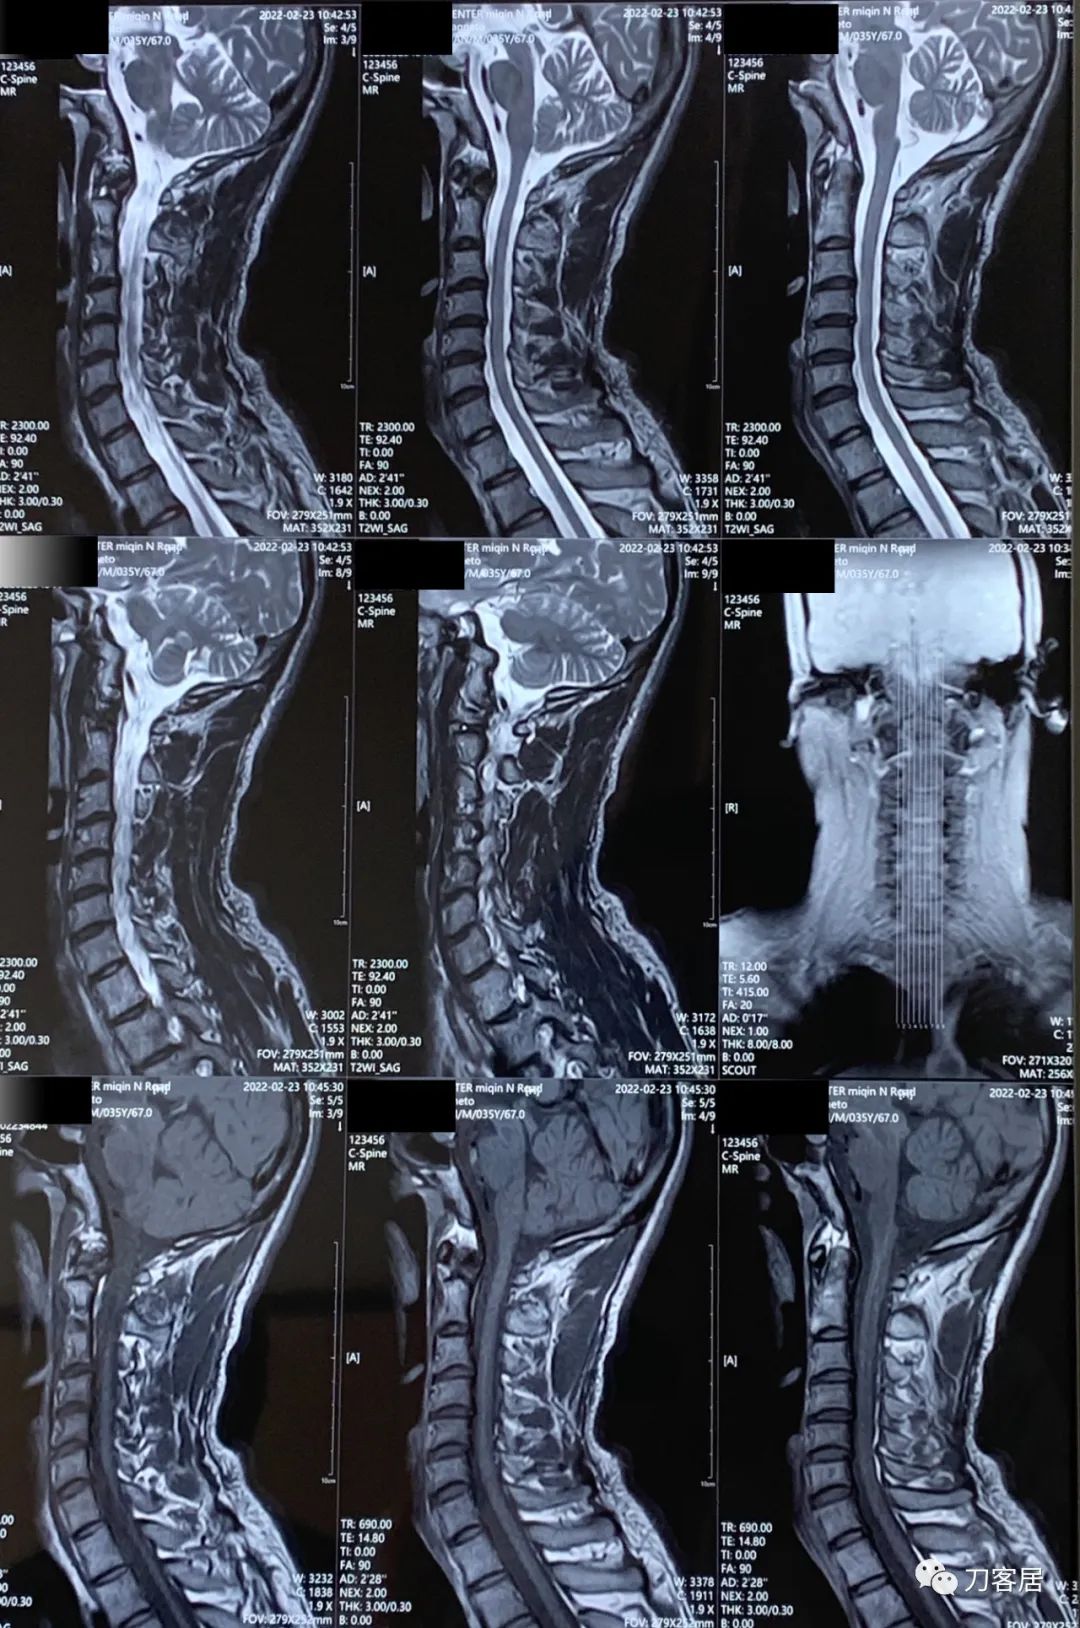

然后建议患者做颈椎和胸椎的MRI检查,看看有无脊髓受压表现。

颈椎及胸椎MRI检查后,并没有发现颈椎管及胸椎管有椎间盘突出,也没有椎管狭窄及脊髓受压。

图4. 20220223颈椎MRI01

图5. 20220223颈椎MRI02

图6. 20220223胸椎MRI01

图7. 20220223胸椎MRI02

图8. 20220223颈椎胸椎MRI报告

所以考虑该患者应该是脊髓本身出问题了,可能是脊髓炎,也可能是脊髓本身我并不知道的其他疾病,导致出现了上位神经元损害的表现。然后建议患者去神经内科会诊。